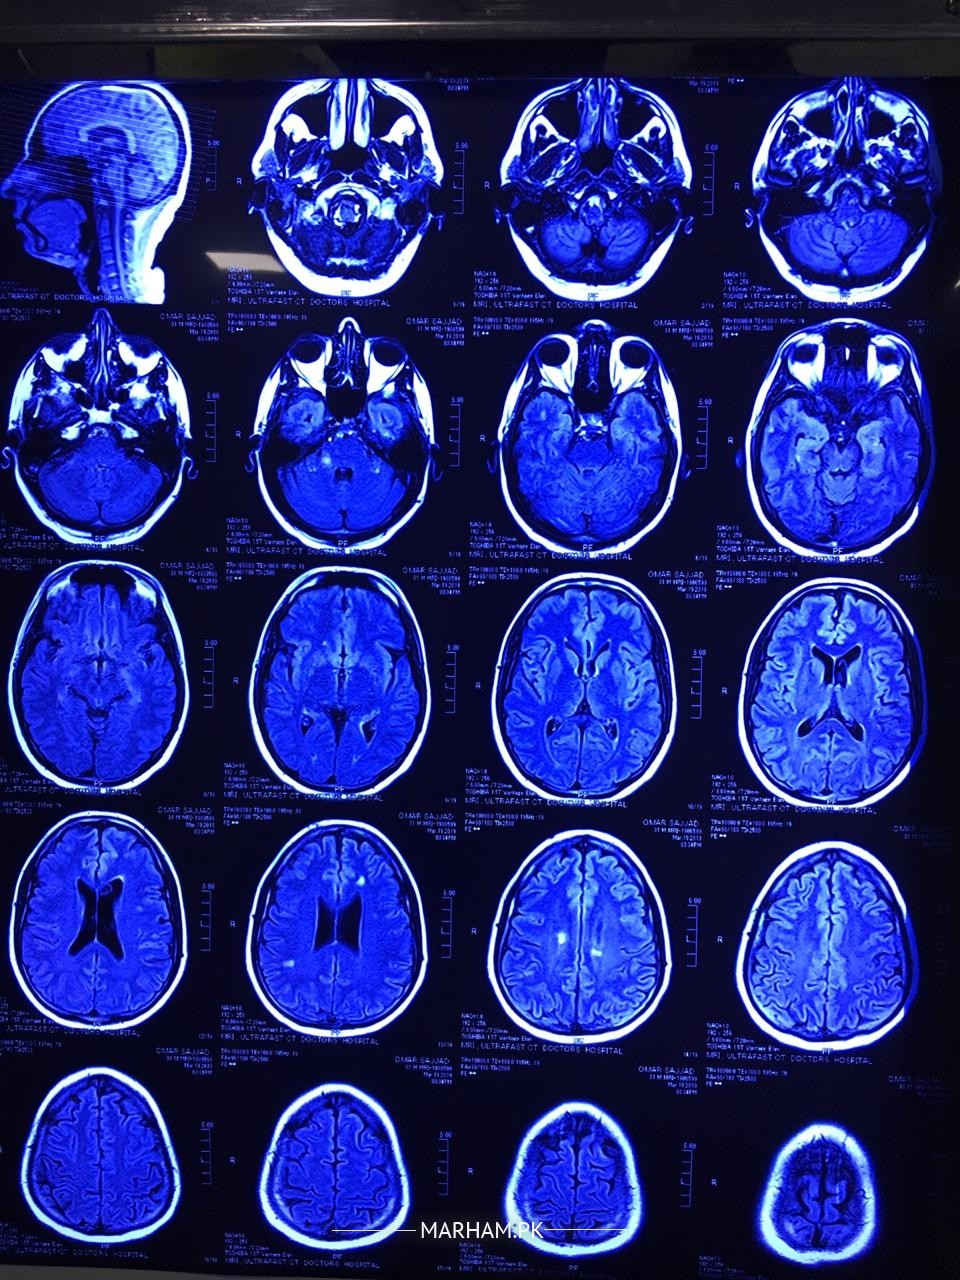

my husband had numbness in his right side of face half head. we consulted a doctor he recommended some tests and MRI. i m attaching some images plz help us understand what is the issue. m attaching all reports and images.

He is a young man and the MRI reports reveal a disease called as Multiple Sclerosis. It a disease in which body's own immune or defence system starts working against own brain tissues. It requires thorough investigations including Lumbar puncture, taking sample of fluid of brain from the spine , and few more tests. It is a chronic disease and you need to consult a neurologist so that appropriate plan of treatment can be discussed in detail.

The MRI scan report seems to suggest a diseases called Multiple Sclerosis. the dis have a deep blue tinge, therefore cannot be reliably commented upon. First the diagnosis needs to be confirmed, with contrast MRI scan and some other tests. then if it's really multiple Sclerosis then a Neurologist will discuss treatment options with you. there are good options available now to control the disease. however, I repeat , most importantly the diagnosis must be confirmed. for that you need to see a neurologist. neurological history and examination are as important as lab tests to diagnose this condition. please show a Neurologist in your city

mri brain finding are suggestive of most likely multiple sclerosis. a disease of demyelinating in nature . need detail history about your husband .